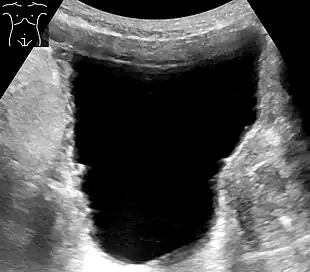

Ultrasonography showing a trabeculated wall, seen as small irregularities mainly at left (superior part). This is strongly associated with urinary retention.[6]